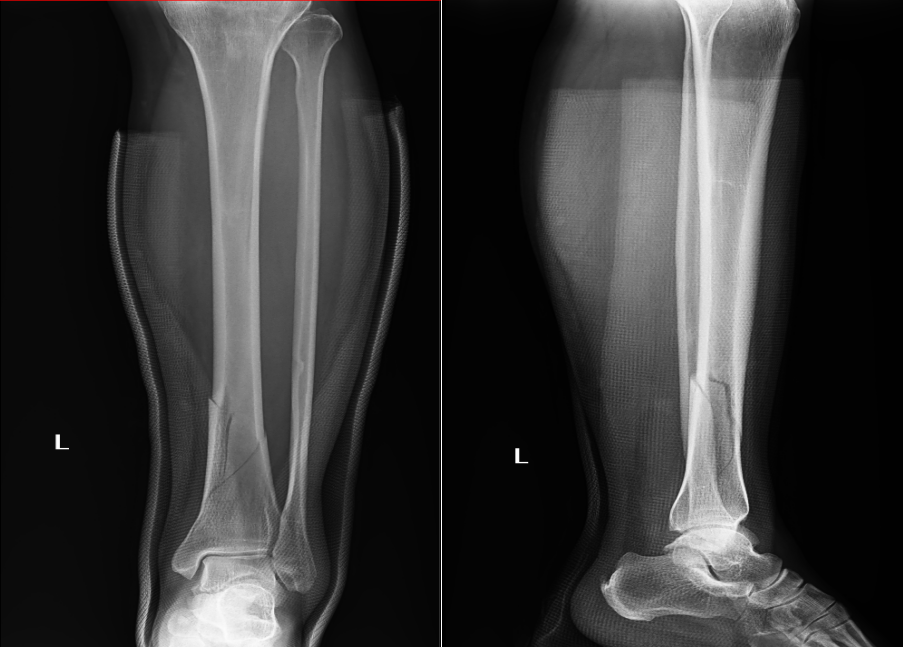

被撞伤致胫骨下段骨折

入院后,八一医院外科医生团队迅速为屈女士进行全面检查,结合其病史、体征及各项检查结果,明确诊断为左侧胫骨下段骨折。通过术前拍片,清晰显示出骨折部位的情况。

术前拍片显示